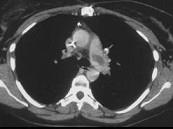

- 单项选择题女,51岁, 心脏手术后,突感胸痛, 结合CT图像,最可能的诊断是 ( )

A、肺栓塞

B、支气管扩张

C、肺水肿

D、肺癌

E、肺不张